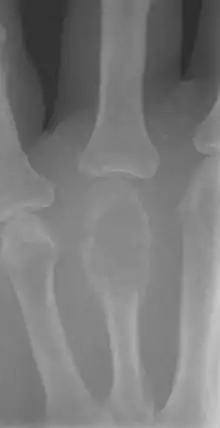

Imaging

On X-ray, giant-cell tumors (GCTs) are lytic/lucent lesions that have an epiphyseal location and grow to the articular surface of the involved bone.[8] Radiologically the tumors may show characteristic 'soap bubble' appearance.[9] They are distinguishable from other bony tumors in that GCTs usually have a nonsclerotic and sharply defined border. About 5% of giant-cell tumors metastasize, usually to a lung, which may be benign metastasis,[10] when the diagnosis of giant-cell tumor is suspected, a chest X-ray or computed tomography may be needed. MRI can be used to assess intramedullary and soft tissue extension.